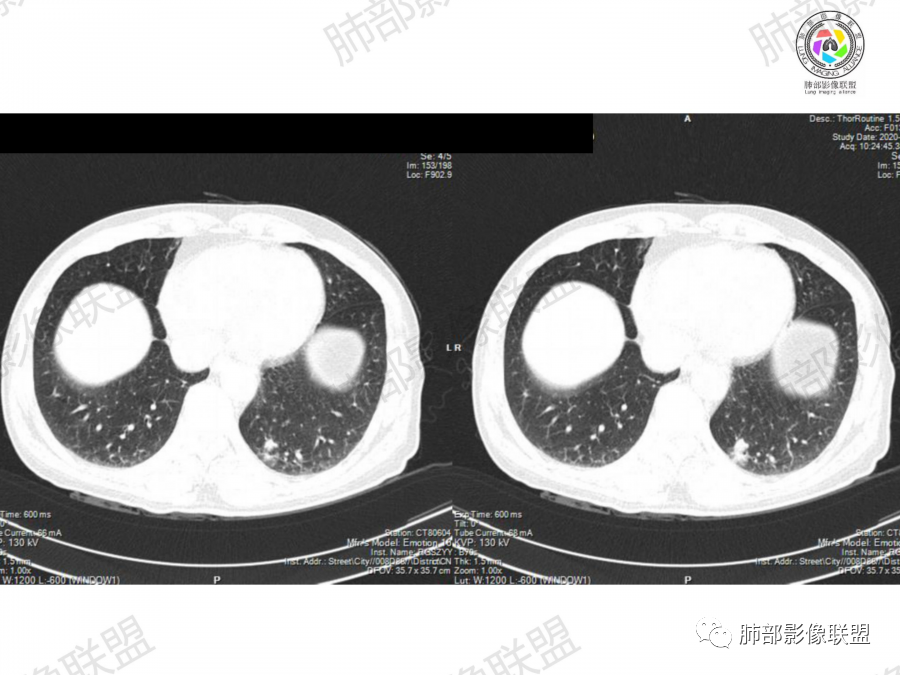

晨读:左肺下叶胸膜下实性结节影边缘毛糙,有毛刺,分叶,近段支气管未见显示,可能堵塞,远端宽基底与胸膜相贴,边缘平直,部分彭隆,病灶局限、单发,无增强,不好判断肿瘤血供,临床男性,63岁,无症状,体检发现,有吸烟史,考虑恶性:腺癌,鳞癌,小细胞肺癌,鉴别:肺隐球菌建议增强及穿刺检查。

老年男性,吸烟史。左下肺外周结节,糊墙,部分边缘平直、部分膀隆,见分叶,支气管截断?部分边缘似乎有GGO,内部情况不详。整体考虑恶性,腺癌可能性大,注意鉴别鳞癌、炎性肉芽肿。

晨读病例,老年人 ,吸烟史,左肺下叶结节影,密度均匀,边缘毛糙,周围可见长毛刺,病灶边缘分叶,局部膨隆,部分边界平直,收缩,病灶相邻胸膜处可见糊墙征象,病灶近肺门处见支气管堵塞,考虑恶性病变,周围型肺癌:鳞癌伴肺不张>腺癌,鉴别隐球,炎性假瘤。

2、影像表现:无肺气肿背景、定位左肺下叶后基底段,不规则结节、与支气管关系不明确,部分边缘平直、部分膨隆,病变与胸膜宽基底相连,病变与胸膜糊墙征,病变周围见细、长、软毛刺,病变密度比较均匀。影像总体倾向炎症、符合肺组织慢性炎症伴机化。